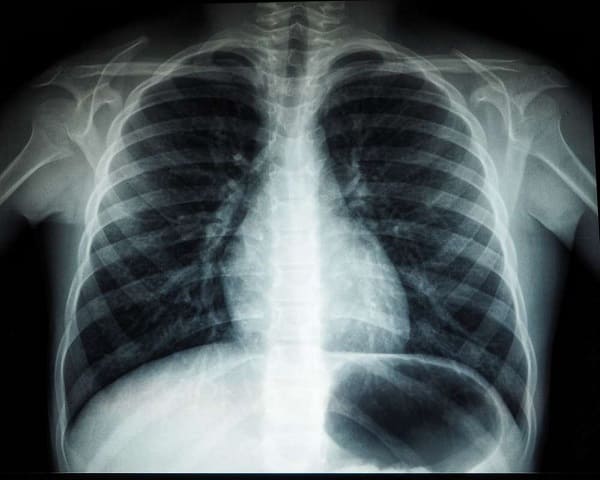

흉부 X-레이 또는 컴퓨터 단층촬영(CT): 폐의 상태를 확인하고 다른 유형의 폐렴과 구별합니다.